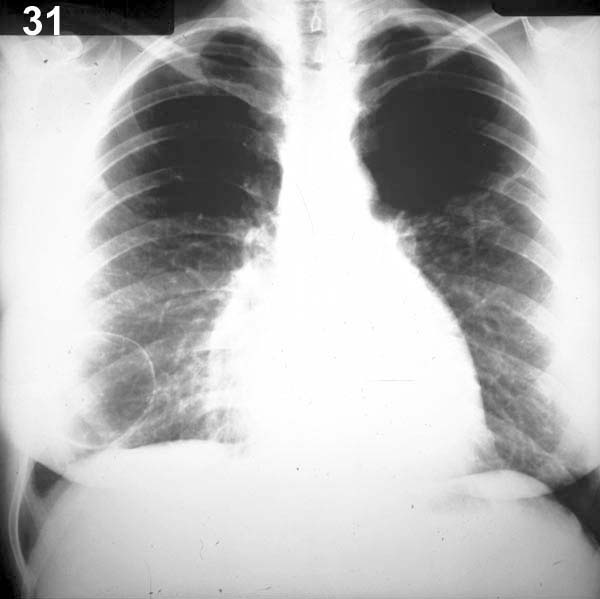

Placa 31